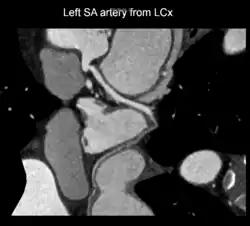

Curved planar reformatted image of sinoatrial nodal artery originating from proximal left circumflex artery. Variant anatomy.

A left S-shaped sinoatrial artery, originating from the proximal left circumflex or LCx artery, has been described as a common variant in approximately 10% of human hearts.[5] This artery is larger than normal and supplies a good part of the left atrium, but also right-sided structures like part of the sinoatrial node and the atrioventricular nodal areas. In this variant, the artery courses in the sulcus between the left superior pulmonary vein and the left atrial appendage where it could be susceptible to injury during catheter or surgical ablation procedures on the left atrium, especially for atrial fibrillation ablation or open-heart cardiac surgery.